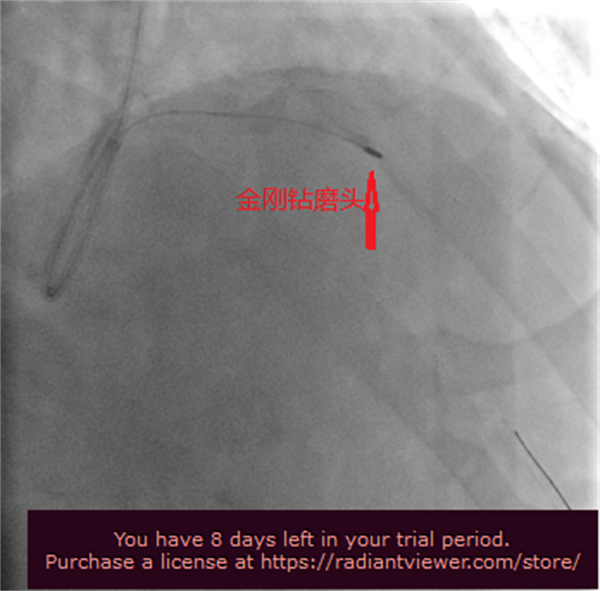

随后在张海涛教授的指导下,李钢、王志勇、鞠静等专家团队紧密配合,采用1.5mm的旋磨头,每次旋磨持续15~30秒,间隔30秒~2分钟,以保证充分清除碎屑。如此反复旋磨,终于打通“隧道”,并在前降支近-中段植入2枚支架,手术顺利完成。

冠状动脉旋磨术是用一枚直径1.25至1.75毫米、嵌有钻石颗粒的橄榄形旋磨头,在导丝引导下进入患者冠状动脉,以每分钟约140,000~190,000rpm的高速旋转的速度打磨阻碍血管通畅的“壁垒”。主要适用于解剖学上高危的病变,如钙化的病灶、开口处病灶、球囊难以扩张的病灶和长段血管病灶等,对手术操作者的技术和经验要求非常高。